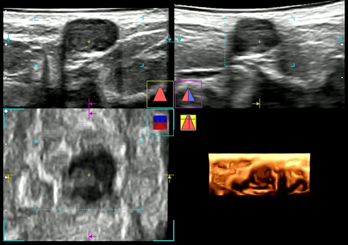

正常乳線の超音波像

Aが縦断面、Bが横断面、

Cが水平面、Dが立体構築した画像

正常乳線の縦断面超音波像を

厚み付き画像で表示

正常乳線の水平面、縦断面、横断面の超音波像をそれぞれ0.5mm間隔のスライスで表示